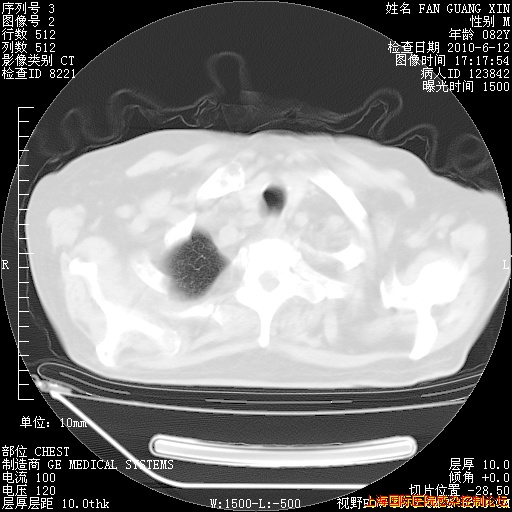

今天复查CT

今天CT

整整相隔30天的肺部CT好像有所好转啊。甲强龙减量第3天,需要观察体温。